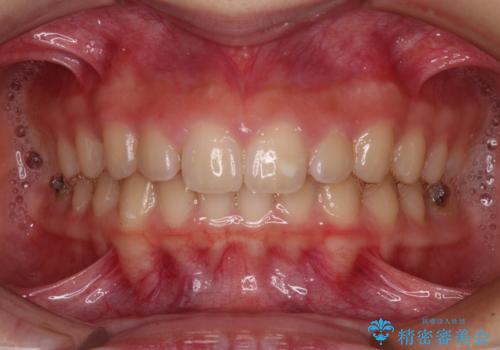

- ヨーロッパにてインビザライン矯正を始めたものの、日本に転居することになり、治療の継続を希望して来院された患者様です。

治療計画に無理がなく、現地担当医と速やかに連絡が取れるとのことで、インビザライン社での転医手続きを行い、継続して治療を行うこととしました。

舌の突出癖により、上下前歯が非接触となっていたため、トレーニングを徹底的に指導し、安定した咬み合わせにより終了させることができました。